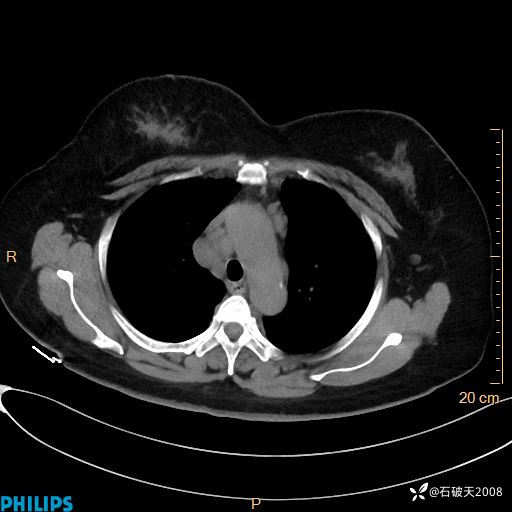

动脉期